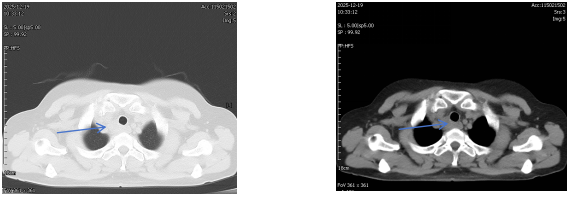

治疗后1月胸部CT

经过胸外科团队的成功采样,医院病理科专家当晚即对穿刺标本进行分析,镜下可见真菌菌丝,形态符合曲霉菌感染,未见恶性肿瘤细胞。“不是癌,是感染!”这个结果让所有人松了一口气。医疗团队随即为患者制定抗真菌治疗方案,经系统治疗后,患者吞咽哽咽感明显缓解,复查影像显示病灶显著缩小。

从影像学高度怀疑恶性肿瘤,到最终明确诊断为曲霉菌感染,这一诊疗过程充分体现了现代精准医疗的价值。通过EBUS-TBNA这一微创技术,患者避免了不必要的创伤性大手术和放化疗。而这场“抽丝剥茧”的背后,是医院放射科、微创中心(第二手术区)、病理科、胸外科等多学科团队紧密协作、高效沟通的结果,彰显了医院在复杂疾病诊疗中的综合实力。